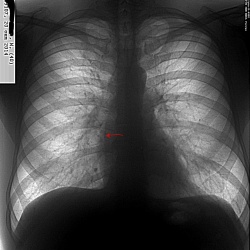

Женщина 1992 г.р. Жалобы на похудение до 5 кг/месяц, кашель с мокротой.

Мой диф ряд: лимфома, саркоидоз, туберкулез. На ваш взгляд, на что больше похоже?